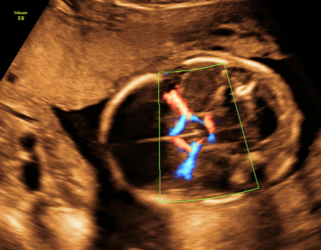

4.分娩前超声检查:超声重点观察指标包括:胎方位、胎儿大小、胎盘及胎儿循环、羊水量、胎盘成熟度、有无胎盘早剥或前置胎盘、脐带有无绕颈、脱垂等。这些指标对临产时医师选择正确的分娩方式,对母亲及胎儿健康平安至关重要。尤其对在整个孕期从未接受超声检查的准妈妈,为了母子的平安,分娩前务必接受一次超声检查。

只需要选择高档二维彩色系统产前超声检查,它包括胎儿结构29张图片,主要观察胎儿发育与结构是否正常。

四维超声检查(动态三维超声检查)只是给宝宝拍了一张照片,对胎儿位置和姿势要求较高,胎儿孕周比较大才能拍的好,不能够评价胎儿的结构和发育情况。如果要求了解宝宝的结构是否正常,只需要选择系统产前超声检查。